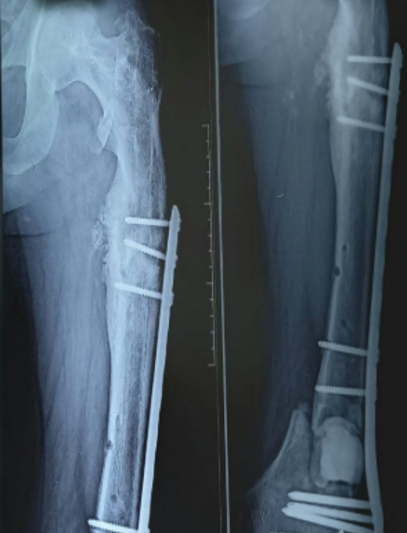

Tras un accidente de tránsito, Yessenia presentó una fractura expuesta con un defecto óseo de 10 cm en su pierna. Había recibido tratamientos previos sin éxito y su movilidad estaba en riesgo.

Con la técnica de osteogénesis por distracción y el uso de un tutor circular Ilizarov, se inició un proceso de regeneración ósea progresiva, acompañado de un seguimiento cercano.

Hoy Yessenia evoluciona favorablemente, conserva movilidad en su rodilla y tobillo, y está recuperando la independencia que pensaba perdida.